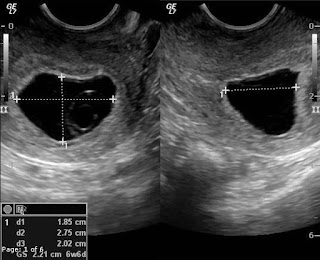

Blighted ovum juga dikenal sebagai kehamilan tanpa embrio. Pada saat terjadi pembuahan, sel-sel tetap membentuk kantung ketuban, plasenta, namun telur yang telah dibuahi (konsepsi) tidak berkembang menjadi sebuah embrio. Pada kondisi blighted ovum kantung kehamilan akan terus berkembang, layaknya kehamilan biasa, namun sel telur yang telah dibuahi gagal untuk berkembang secara sempurna. Maka pada ibu hamil yang mengalami blighted ovum, akan merasakan bahwa kehamilan yang dijalaninya biasa-biasa saja, seperti tidak terjadi sesuatu, karena memang kantung kehamilan berkembang seperti biasa. Pada saat awal kehamilan, produksi hormon HCG tetap meningkat, ibu hamil ketika di tes positif, juga mengalami gejala seperti kehamilan normal lainnya, mual muntah, pusing-pusing, sembelit dan tanda-tanda awal kehamilan lainnya. Namun ketika menginjak usia kehamilan 6-8 minggu, ketika ibu hamil penderita blighted ovum memeriksakan kehamilan ke dokter dan melakukan pemeriksaan USG, maka akan terdeteksi bahwa terdapat kondisi kantung kehamilan berisi embrio yang tidak berkembang. Jadi, gejala blighted ovum dapat terdeteksi melalui pemeriksaan USG atau hingga adanya perdarahan layaknya mengalami gejala keguguran mengancam (abortus iminens) karena tubuh berusaha mengeluarkan konsepsi yang tidak normal.

Blighted Ovum hanya dapat dideteksi dengan pemeriksaan USG transvaginal. Sayangnya, agar gambar objek (janin) terlihat lebih jelas, USG transvaginal ini hanya dapat dilakukan saat kantung kehamilan sudah besar, yaitu dengan diameter diatas 16 milimiter atau saat usia kandungan menginjak 6-7 minggu.